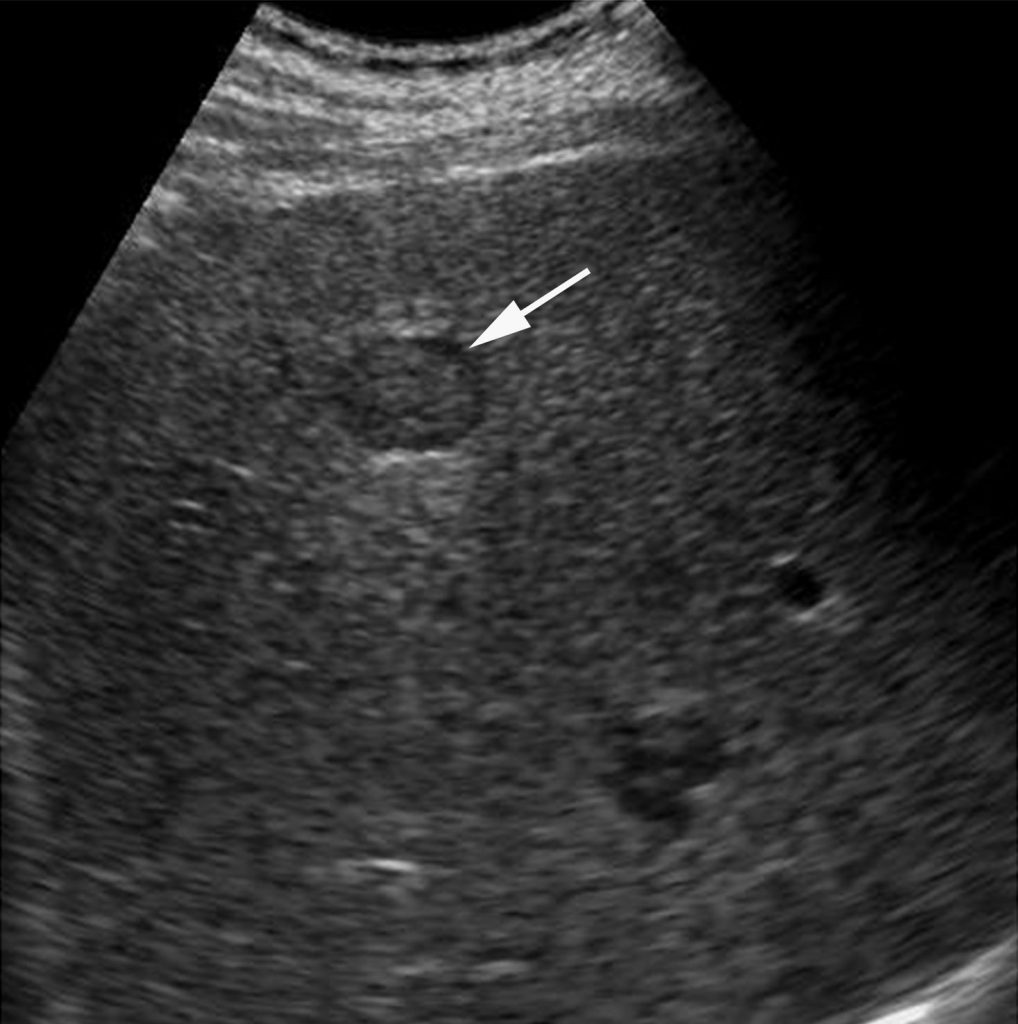

C. Nodules sur cirrhose

De nombreux nodules sont présents dans un foie de cirrhose : des nodules de régénération, des nodules dysplasiques et des tumeurs malignes. L’objectif est de caractériser ces nodules pour diagnostiquer le plus précocement possible les carcinomes hépatocellulaires (cf. chapitre 16) (figure 5.5).

Fig. 5.5 Identification d’un nodule (flèche) lors d’une échographie de surveillance d’un foie de cirrhose.

Ce nodule est possiblement un carcinome hépatocellulaire et doit être caractérisé par IRM en première intention (cf. chapitre 16).

Source : CERF, CNEBMN, 2022.